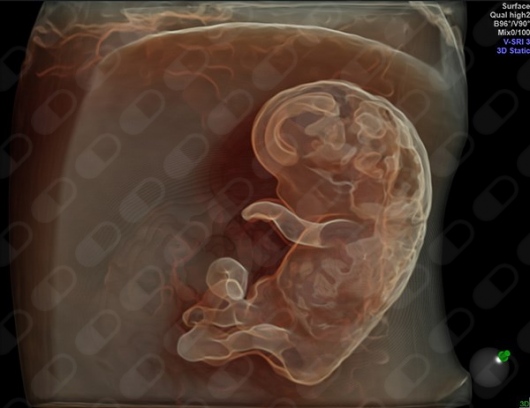

Ecografía 5D

El centro acaba de adquirir el mejor ecógrafo existente en el mercado, el ecógrafo Voluson E10 BT 2018, que permite realizar con máxima fiabilidad todas las ecografías de embarzo (1er, 2 trimestre, EBA-creening, 3er trimestre....) asímismo la 5HD LIVE y la novedísima eco 6D desde la primera hasta la última ecografía del embarazo por un precio muy asequible. Actualmente es el único ecógrafo existente en Barcelona, por lo que el centro se pone en primera linea de diagnóstico prenatal